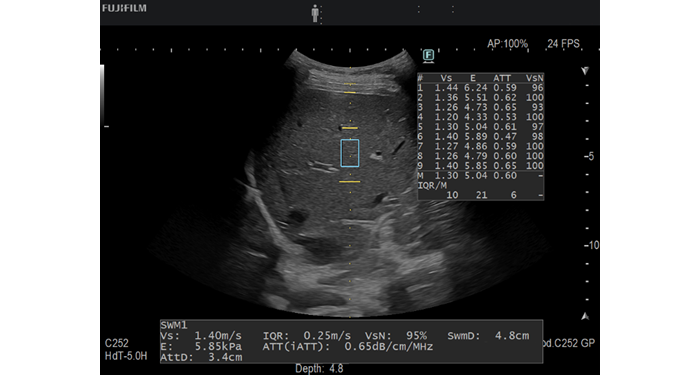

iATT機能は肝臓内の超音波減衰量を非侵襲的に計測し、肝脂肪の定性的な評価指標(ATT)を提供してきました。従来のATTに加え、後方散乱係数と信号のばらつきを考慮した指標Steatosis Backscatter Index(SBSI)*2を表示可能です。

iATTは、肝臓内における超音波の減衰量を非侵襲的に計測し、肝臓の脂肪量を定性的に評価する指標(ATT)を提供する機能です。被検者への負担が少なく肝脂肪化の程度を評価できるため、定期検査などで脂肪肝の早期発見に貢献します。

進化したiATTは、計測位置を変更できるようになり、肝臓の計測においてばらつきの要因となる皮下脂肪を避け、World Federation for Ultrasound in Medicine and Biology(WFUMB)ガイドラインに準拠した計測位置の設定が可能となりました。また、従来のATTに加え、後方散乱係数と信号のばらつきを考慮した指標SBSI(Steatosis Backscatter Index)*2を表示可能です。

計測位置の変更ができ、計測のばらつきの要因である皮下脂肪を避け、WFUMBガイドラインに準拠した計測位置の設定が可能。ATTに加えて、後方散乱係数と信号のばらつきを考慮した指標SBSI(Steatosis Backscatter Index)*2を表示可能。